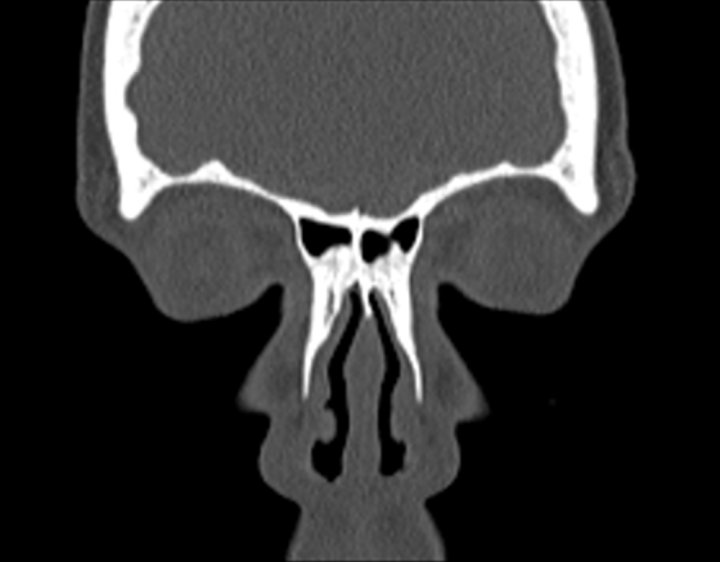

003